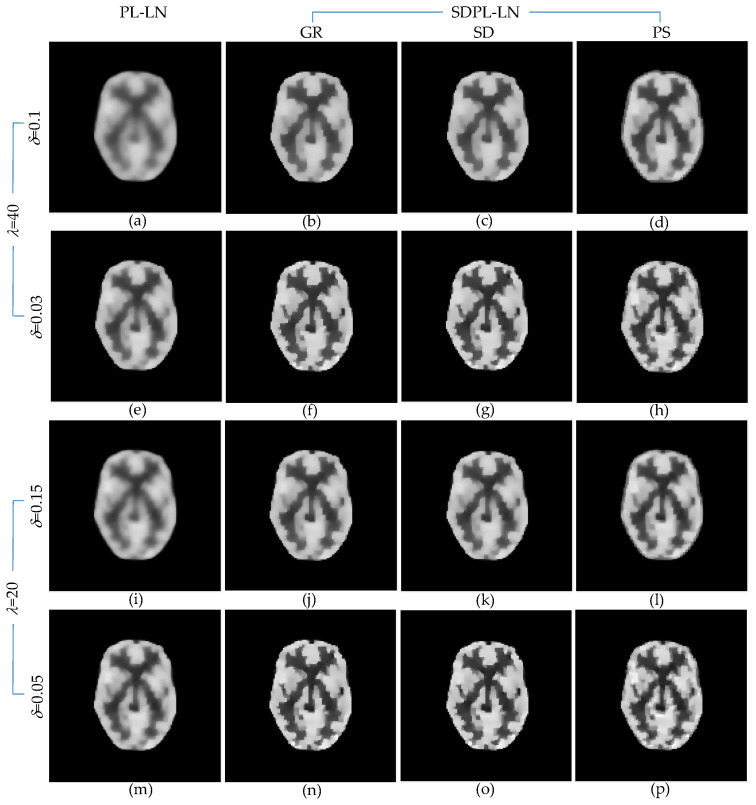

Figure 6 shows the anecdotal PL and SDPL reconstructions using the LN penalty function. The figure comprises four groups of results, each corresponding to a different parameter setting. Specifically, Figure 6a–d shows the results obtained with high λ and high δ, Figure 6e–h with high λ and low δ, Figure 6i–l with low λ and high δ, and Figure 6m–p with low λ and low δ. Within each row, the reconstruction methods are displayed from left to right as PL-LN and SDPL-LN (GR, SD, and PS), respectively. A qualitative comparison of the results in Figure 6 clearly reveals that the SDPL method better preserves fine details than the standard PL method.

Figure 6.

Anecdotal reconstructions using PL-LN and SDPL-LN with two different (high and low) levels of λ and two different (high and low) levels of δ for each λ. (The results in the first column (a,e,i,m) are PL-LN reconstructions, whereas the rest of the results are SDPL-LN reconstructions). (a–h) λ = 40 (i–p) λ = 20 (a–d) δ = 0.1; (e–h) δ = 0.03; (i–l) δ = 0.15; (m–p) δ = 0.05.

To elaborate further, when both λ and δ are excessively large (Figure 6a–d), the PL result in Figure 6a appears over-smoothed, whereas the SDPL results in Figure 6b–d exhibit enhanced detail. By reducing the value of δ while keeping λ fixed, the SDPL result in Figure 6e becomes sharper than its PL counterpart in Figure 6a. Similarly, the SDPL results in Figure 6f–h, like those in Figure 6b–d, demonstrate superior preservation of fine details compared to the result in Figure 6e. Based on the observations from Figure 6a–h, we tentatively conclude that the SDPL method effectively mitigates the over-smoothing issue of the PL method for relatively high λ values. As expected, when the smoothing parameter λ is decreased, the results become sharper and exhibit more details. However, even in this case, the SDPL method further enhances reconstruction accuracy by better preserving fine details, as evident in Figure 6i–p. In an extreme case, where the values of both λ and δ are very small, the results become noisy, a phenomenon that is not specific to the SDPL method but holds true for any regularization method. In conclusion, the SDPL method surpasses the standard PL method in effectively preserving fine details when the hyperparameters are chosen to be sufficiently large, ensuring effective noise suppression.